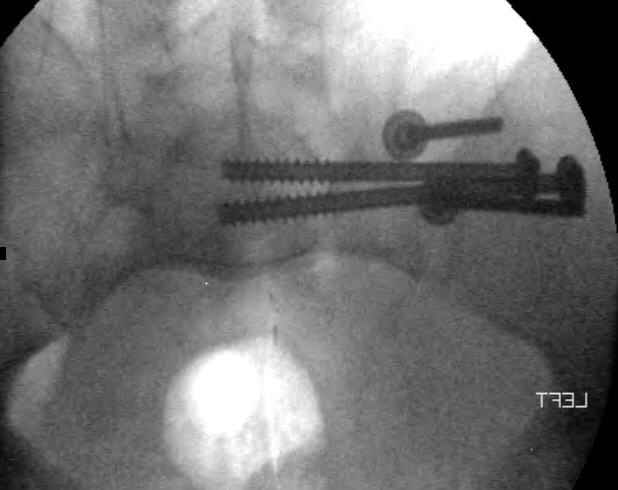

Hello gentlemen- Case is 52 YO male, fell out of treestand while deerhunting. He is 6 ft, approx. 260-275 lbs. Was hemodynamic unstable at local ER, sent to our Trauma center where circumferential pelvic binder placed and pt. stabilized with fluid, blood, and rewarming. Angiography not performed. An extraperitoneal bladder disruption was found, uro elected to treat non-operatively. Initial xray (not shown) demonstrated 5-7 cm wide at symphysis and SI joint. The first image attached is of CT once binder is in place. On post trauma day 5 the pt was taken to OR for ORIF of his iliac wing fracture and SI dislocation. The swelling/3rd spacing of fluid in the area of symphysis was profound, but quite acceptable posteriorly. Patient was prone for procedure, as I thought too difficult to fix the wing in lateral position. Of course the repair of wing was easy, but reduction of SI very demanding. The Floro images document the residual lack of reduction. That was the closest I could get it using 6mm joystick in wing, and clamp on sacrum and clamp through notch. The fixation was (initially) rigid. Anterior ex fix with supra-acetabular pins was placed due to condition of soft tissues, massive "beer-belly" overhanging the crest. Post trauma day ten patient's xray shows failure of posterior construct. Plan was to perform revision orif once soft tissues resolve considerably for full anrterior fixation and posterior fixation. However, while Im away for holiday (on Post trauma day 15), pt is developing septic clinical appearance, and trauma suspects pelvic abcess near symphysis and performs I and D - finds nothing but no primary closure performed. Posterior tissues/incision continue to look healthy. Now is post trauma day 17, pt is still tubed/on dopamine/and wbc still elevated, anterior incision still packed open. Clearly must get to bottom of possible sepsis, but then what? Thanks for you time - sorry for such lengthy clinical description. Thomas Schaller Kalamazoo, Michigan

5. Your caudal iliosacral screw is/was in his spinal canal... it's low and posterior and the lateral fluoro image confirms this... a postop CT will show it (or it's trail at this point)... canal screws do not hold.

6. Frames (even fancy new-style low ones) have poor mechanical stability when compared to symphyseal internal fixation...unstable rings in fat (and skinny) folks demand stable anterior and posterior stabilities... a frame

can't get you there... consider it a helper/support at best.